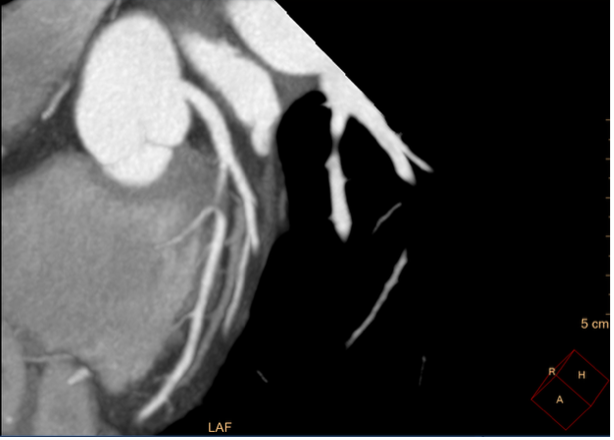

Relevant Test Results Prior to Catheterization

Coronary computed tomography angiography (CCTA) revealed a focal lesion stenosis in the mid-left anterior descending (LAD) artery, without significant disease in the remaining coronary vessels. Based on these findings, the patient was diagnosed with stable angina and referred for invasive coronary angiography to further characterize the lesion and determine the optimal revascularization strategy.